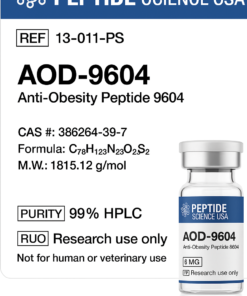

HPLC Adipotide (FTPP) Certificate